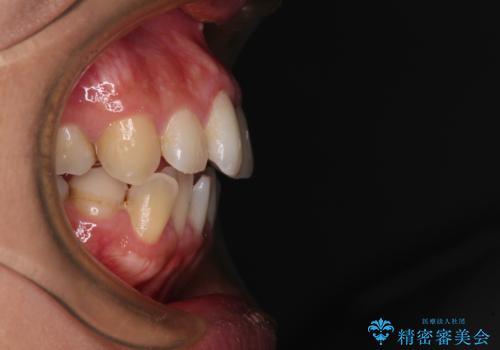

- 右下の欠損部の治療を希望して来院された患者様です。

部分矯正を行った後にインプラント埋入と手前の歯の根管治療を行い、その後補綴治療を行うこととしました。

治療途中より、上の歯や反対側の銀歯、上顎前歯の色合いや下顎前歯のデコボコが気になってきたため、全てを治療することとしました。